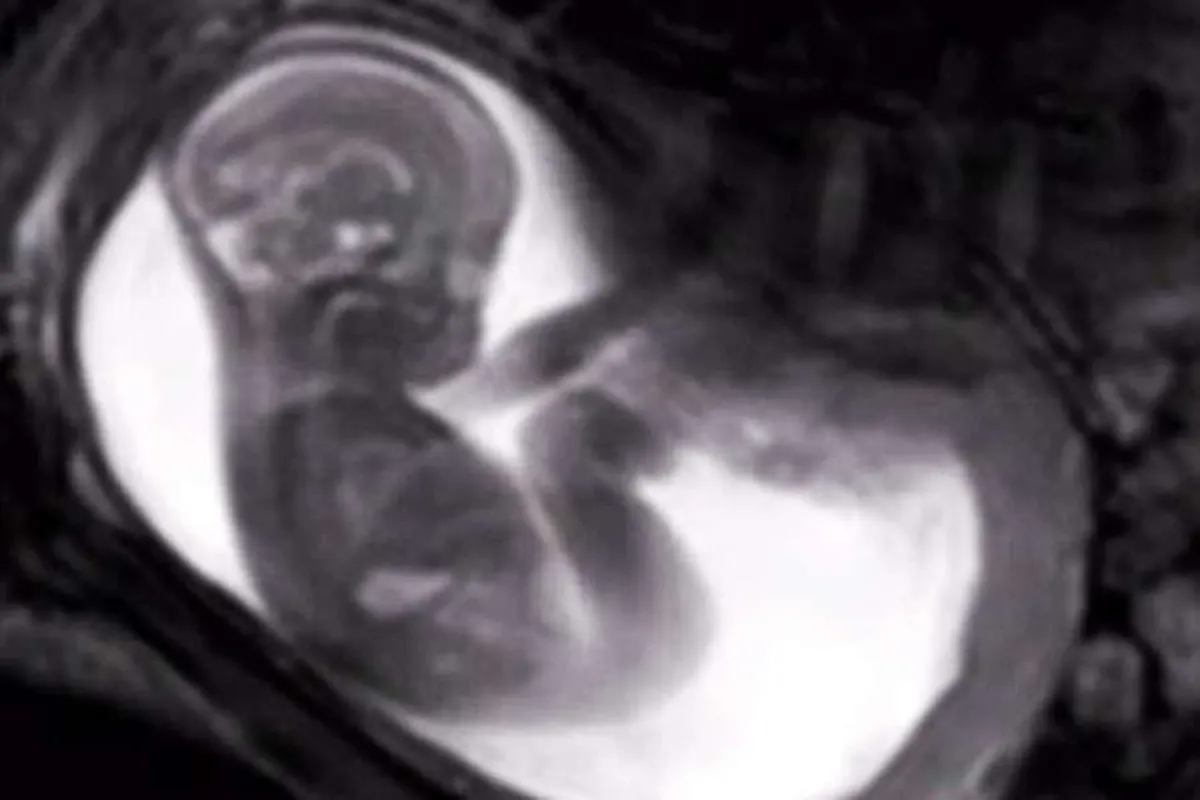

ضجّت مواقع التواصل الاجتماعي بفيديو مميز لجنينٍ في رحِم والدته، سُجّل عبر استخدام تكنولوجيا جديدة.

وصُوّر الفيديو عبر تقنيةِ المجالات المغناطيسية والموجات اللاسلكية، التي تُستخدم لالتقاط صورة عالية الجودة للجنين، وهو في رحم والدته.

ويظهر الفيديو،الذي صوّر في الأسبوع الـ20 من الحمل، الحبلَ السرّي الذي يربط بين الجنين ووالدته بشكل واضح، كذلك يظهر الجنين وهو يحرّك ذراعيه ورأسَه، ويوجّه الركلات لأمه.

وقد صمّم الخبراء الطبّيون في لندن، الذين يعملون على مشروع iFIND، هذه التكنولوجيا الحديثة، MRI scan، لتحسين عمليات الفحص التي تقام قبل الولادة.